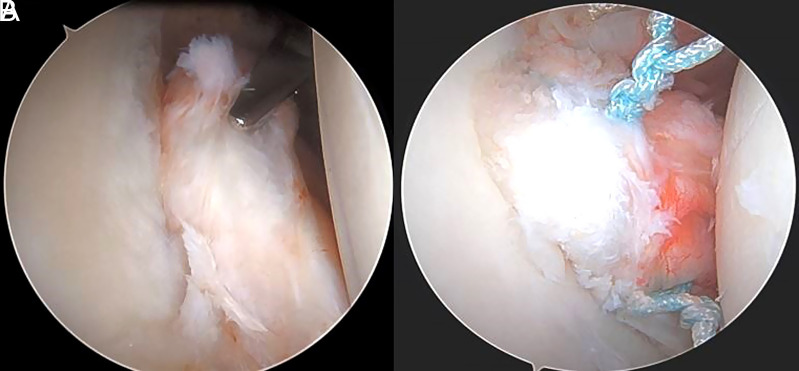

Abstract Image